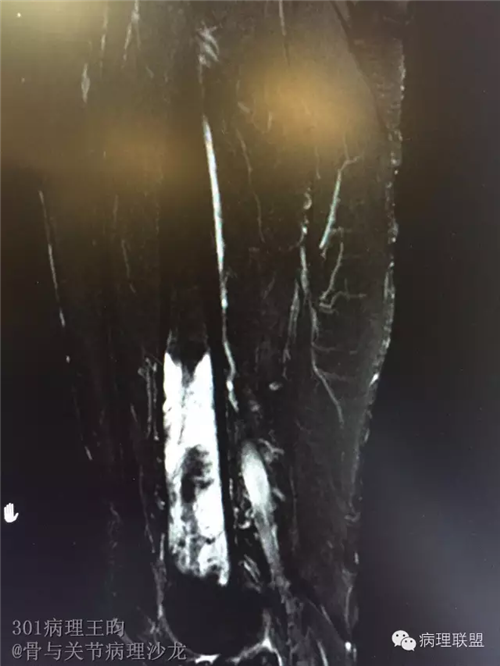

右股骨髓内高分化低级别骨肉瘤or骨纤维异常增殖症(Fibrous Dysplasia)?

男,36岁,活动后疼痛,发现右股骨远端肿瘤。